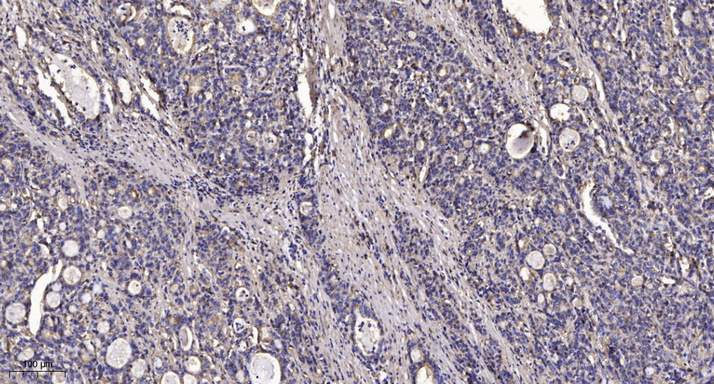

Main InformationTargetFKBP1A/BHost SpeciesRabbitReactivityHuman, Mouse, RatApplicationsIHC, IF, WBMW130kD (Observed)Conjugate/ModificationUnmodifiedDetailed InformationRecommended Dilution RatioIHC 1:50-200; WB 1:500-2000; IF 1:50-200FormulationLiquid in PBS containing 50% glycerol, 0.5% BSA and 0.02% sodium azide.SpecificityThis antibody detects endogenous levels of human FKBP1A/BPurificationThe antibody was affinity-purified from rabbit antiserum by affinity-chromatography using epitope-specific immunogen.Storage-15°C to -25°C/1 year(Do not lower than -25°C)Concentration1 mg/mlMW(Observed)130kDModificationUnmodifiedClonalityPolyclonalIsotypeIgGAntigen&Target InformationImmunogen:Synthesized peptide derived from human FKBP1A/B AA range: 26-75Specificity:This antibody detects endogenous levels of human FKBP1A/BProtein Name:FKBP1A/BBackground:The protein encoded by this gene is a member of the immunophilin protein family, which play a role in immunoregulation and basic cellular processes involving protein folding and trafficking. The protein is a cis-trans prolyl isomerase that binds the immunosuppressants FK506 and rapamycin. It interacts with several intracellular signal transduction proteins including type I TGF-beta receptor. It also interacts with multiple intracellular calcium release channels, and coordinates multi-protein complex formation of the tetrameric skeletal muscle ryanodine receptor. In mouse, deletion of this homologous gene causes congenital heart disorder known as noncompaction of left ventricular myocardium. Multiple alternatively spliced variants, encoding the same protein, have been identified. The human genome contains five pseudogenes related to this gene, at least one of which is transcribed. [provided bFunction:Catalytic activity:Peptidylproline (omega=180) = peptidylproline (omega=0).,enzyme regulation:Inhibited by both FK506 and rapamycin.,Function:May play a role in modulation of ryanodine receptor isoform-1 (RYR-1), a component of the calcium release channel of skeletal muscle sarcoplasmic reticulum. There are four molecules of FKBP12 per skeletal muscle RYR. PPIases accelerate the folding of proteins. It catalyzes the cis-trans isomerization of proline imidic peptide bonds in oligopeptides.,similarity:Belongs to the FKBP-type PPIase family.,similarity:Belongs to the FKBP-type PPIase family. FKBP1 subfamily.,similarity:Contains 1 PPIase FKBP-type domain.,Cellular Localization:Cytoplasm, cytosol . Sarcoplasmic reticulum membrane ; Peripheral membrane protein ; Cytoplasmic side .Tissue Expression:Lung,PCR rescued clones,Placenta,Platelet,